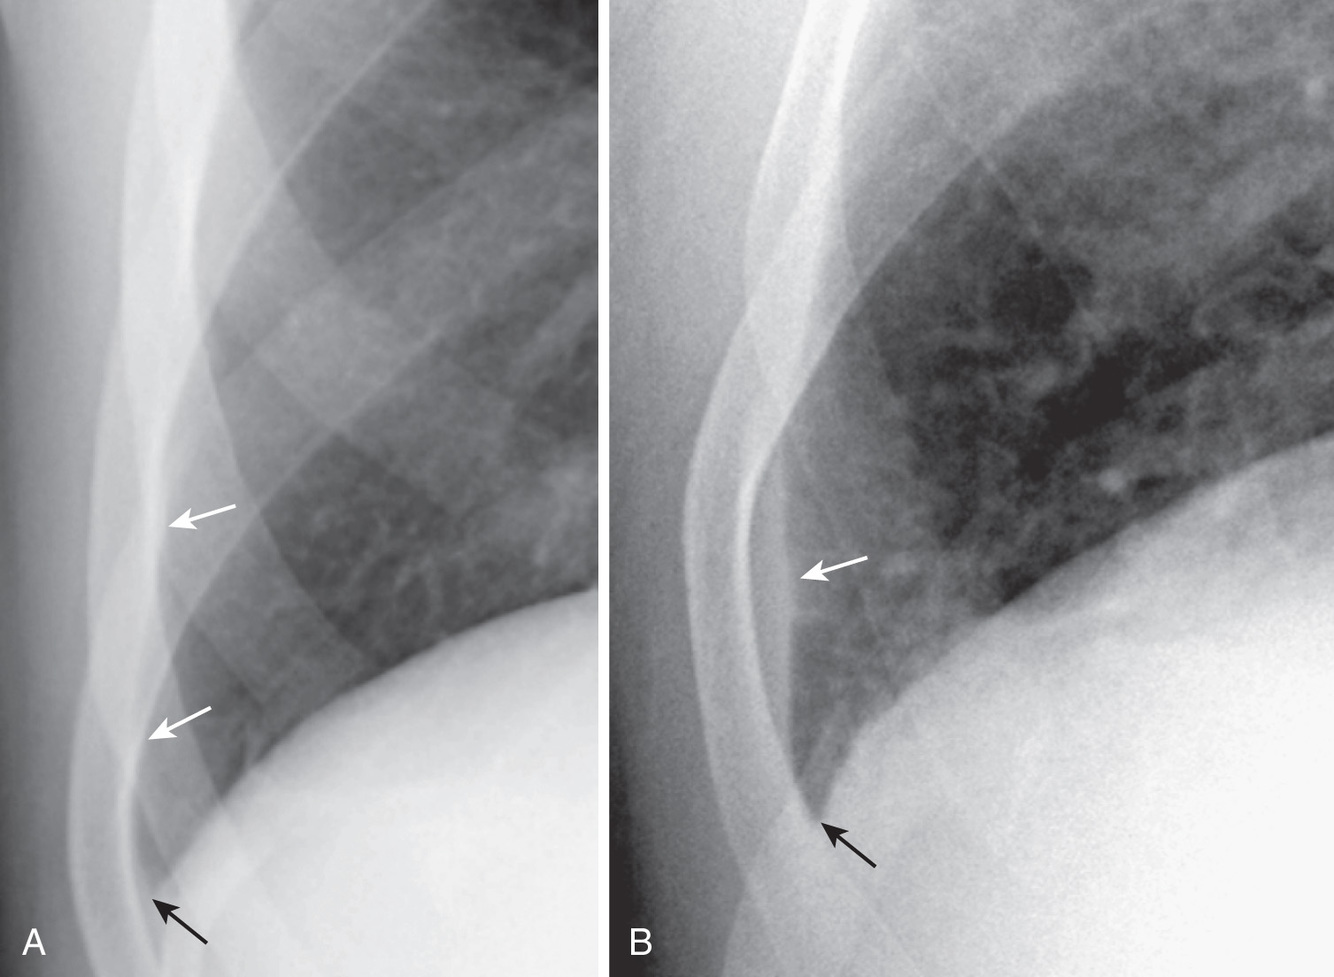

What is going on in this CXR?

Here the left costophrenic angle appears blunted, but the whole left lower lobe-diaphragmatic interface is also slanted.

Don’t be fooled into thinking that this is a pleural effusion. The angle is blunted here because of pleural thickening and fibrosis. The ski slope sign can help you differentiate them: the surface is slanted rather than concave like a meniscus.